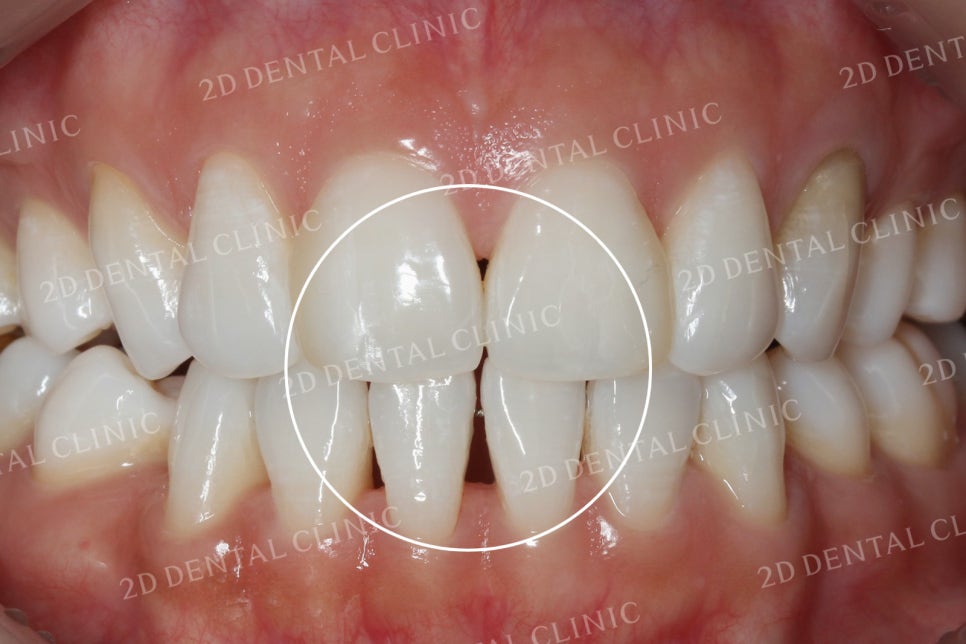

치아틈새를 완벽하게 메꾸는 방법, 치간이개로 인한 블랙트라이앵글을 쎄라필름(TheraFilm)으로 완전히 삭제하기! 입니다. 오늘 소개해드릴 Case의 환자분께서는 치아 사이의 틈! 치간이개로 인한 블랙트라이앵글이 심각한 상태로 진행되신 상태였습니다. 이러한 블랙트라이앵글은 나이가 들면서 서서히 약해지는 구강 내 지반, 잇몸, 잇몸 뼈들이 퇴축함으로써 자주 발생하게 됩니다. 이에 따라 잇몸이 내려 앉고 치아의 뿌리가 드러나면서 시리고 통증을 유발하게 됩니다. 아래의 사진을 보시면서 자세한 설명을 이어가겠습니다.

환자분의 쎄라필름 시술 전 치아 사진입니다.

치아의 상태를 보시면 중간 중간 치아 사이의 틈새가 까맣게 보이는 것을 확인하실 수 있습니다.

치아의 뿌리가 드러나게 되면 잇몸이 치아를 지탱하는 힘이 약해짐은 물론이며,

시린이, 풍치 등 여러 구강질환을 유발할 수 있습니다.

교합 시 하악의 중절치 부근에 블랙트라이앵글이 심하게 발생한 모습입니다.

상악 역시 중절치의 치간이개가 많이 진행된 모습이네요.